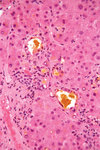

Bilirubin

Bile crystals in liver

Granulation tissue, poorly formed granuloma and giant Langerhans type cells